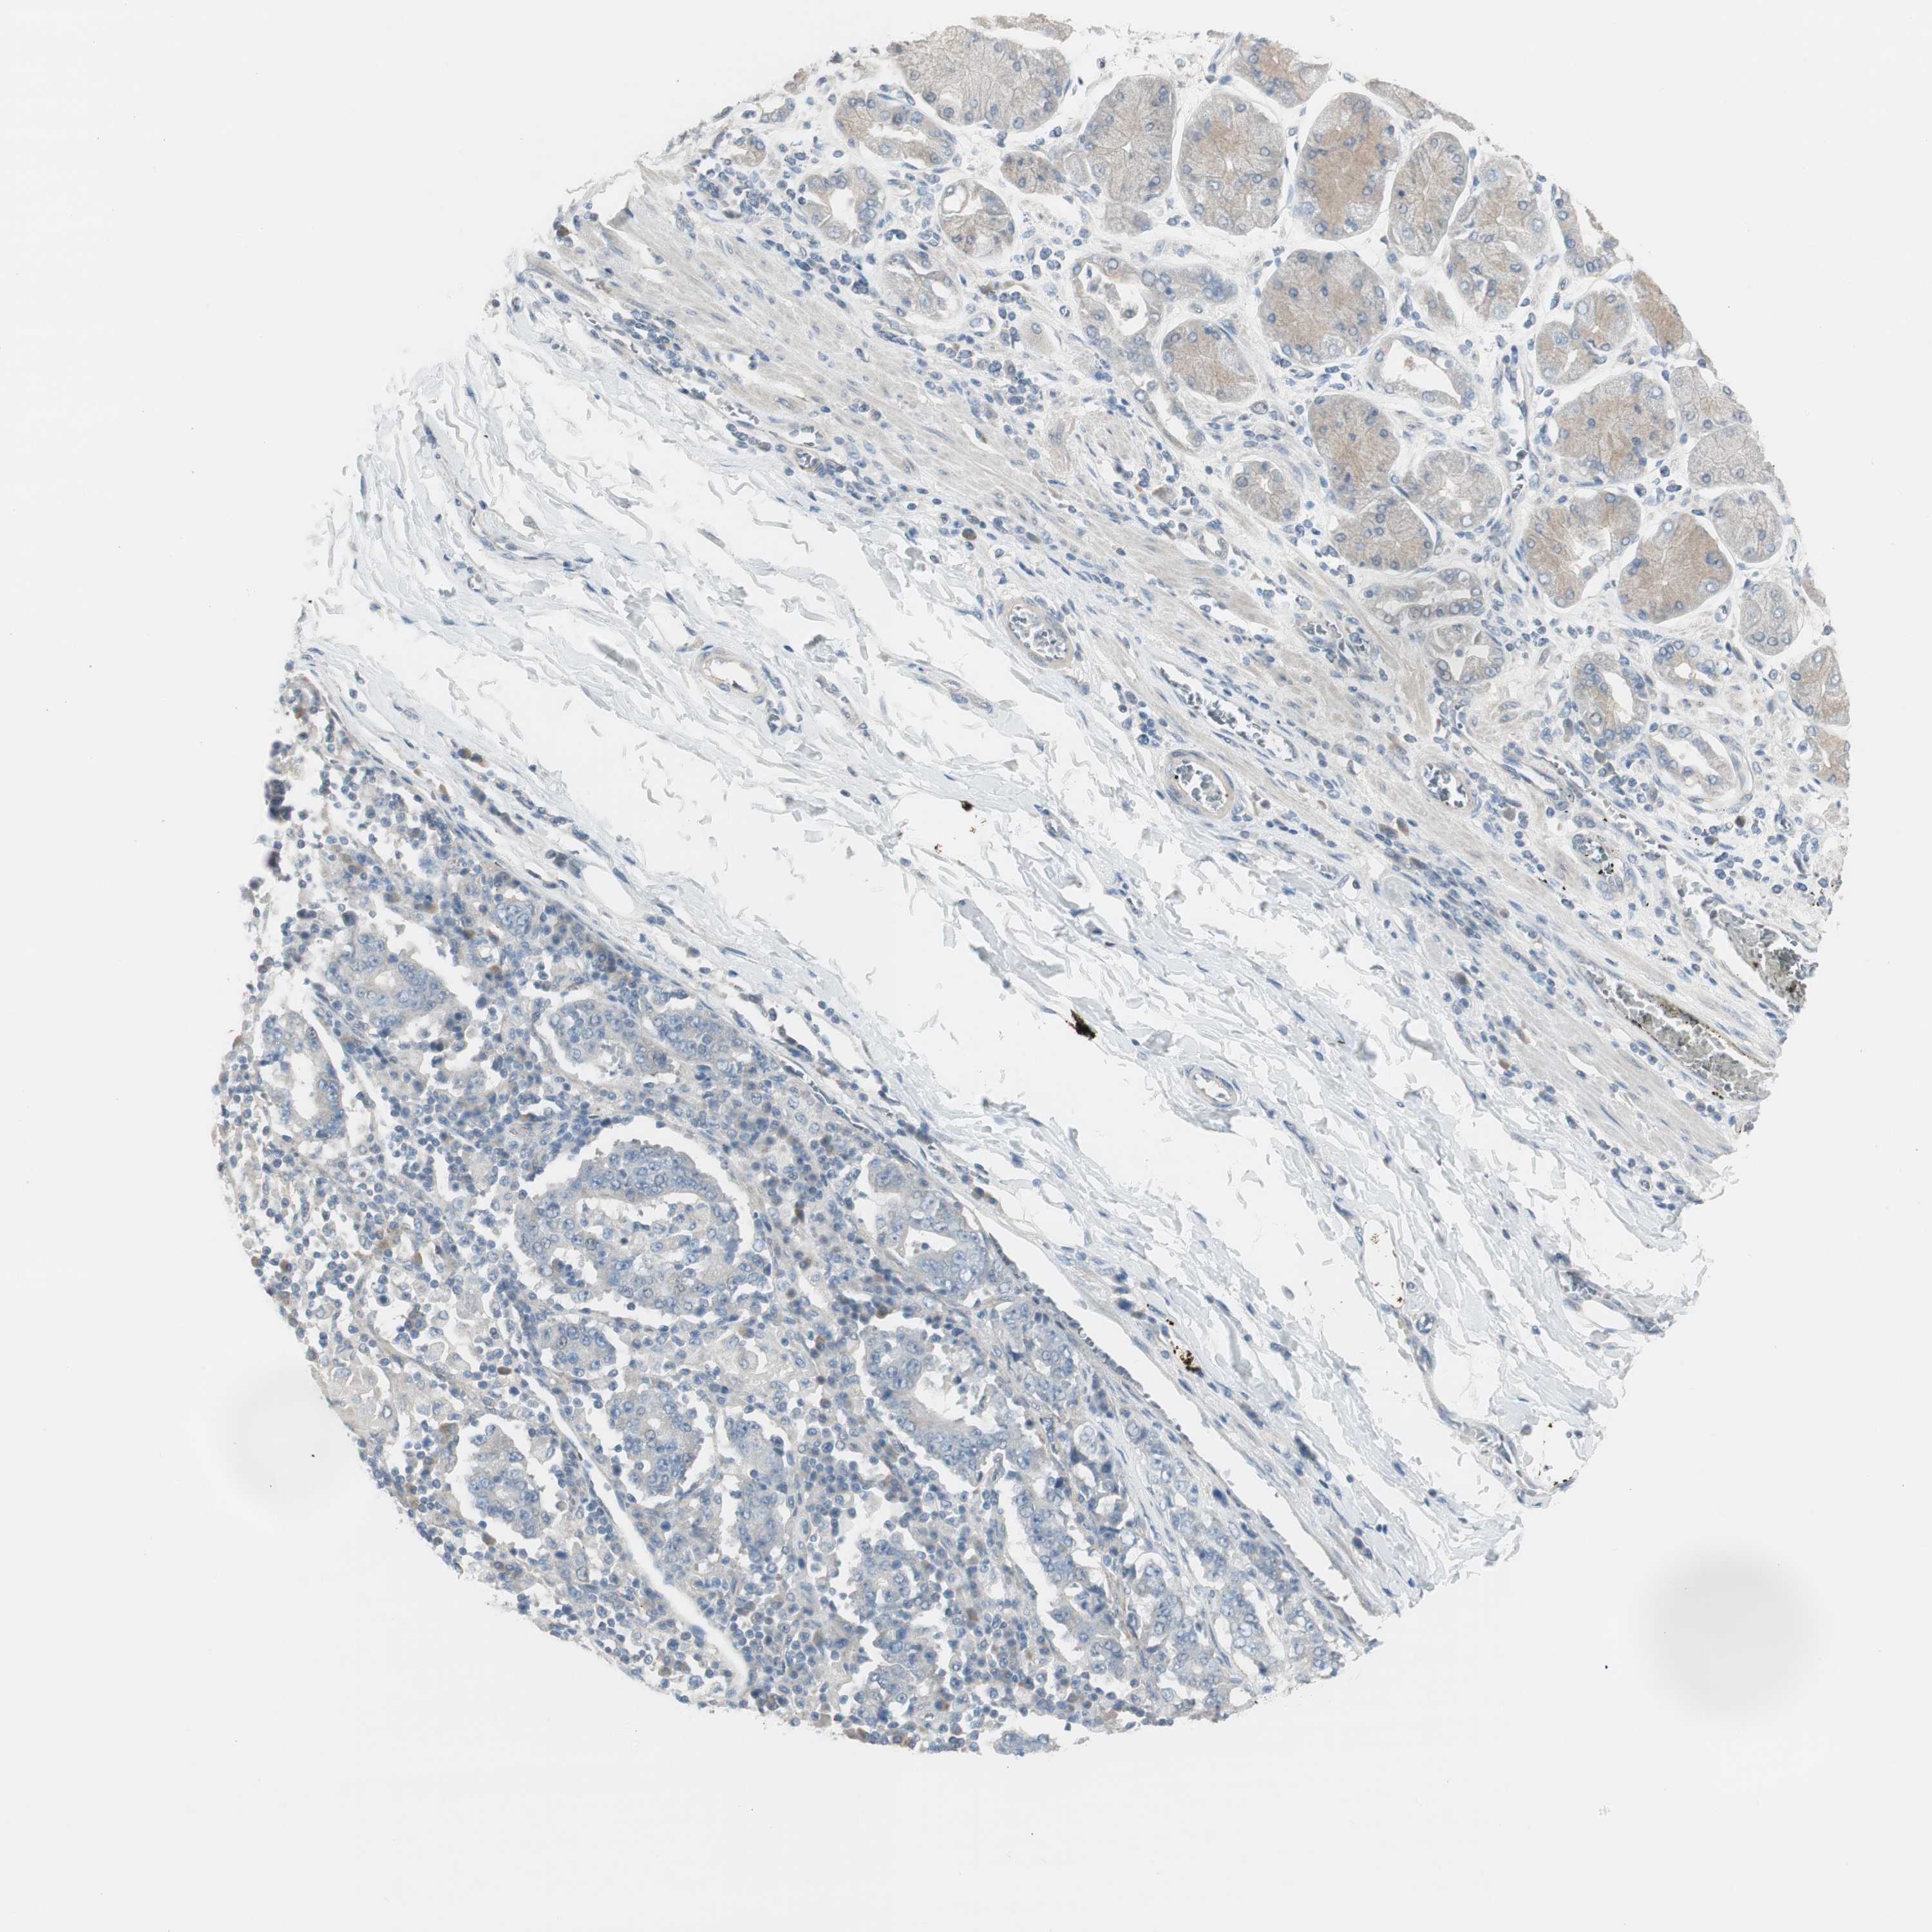

STOMACH CANCER - Protein expressioni

A mouse-over function shows sample information and annotation data. Click on an image to view it in a full screen mode. Samples can be filtered based on level of antibody staining by selecting one or several of the following categories: high, medium, low and not detected. The assay and annotation is described here.

Note that samples used for immunohistochemistry by the Human Protein Atlas do not correspond to samples in the TCGA dataset.

Antibody stainingi

Antibody staining in the annotated cell types in the current human tissue is reported as not detected, low, medium, or high, based on conventional immunohistochemistry profiling in selected tissues. This score is based on the combination of the staining intensity and fraction of stained cells.

Each image is clickable and will lead to virtual microscopy that enables deeper exploration of all samples and also displays staining intensity scores, fraction scores and subcellular localization as well as patient and tissue information for each sample.

Antibody HPA008055

Staining

High

Medium

Low

Not detected

Intensity

Strong

Moderate

Weak

Negative

Quantity

>75%

75%-25%

<25%

None

Location

Nuclear

Cytoplasmic/membranous

Cytoplasmic/membranous,nuclear

Adenocarcinoma, NOS

Adenocarcinoma, High grade